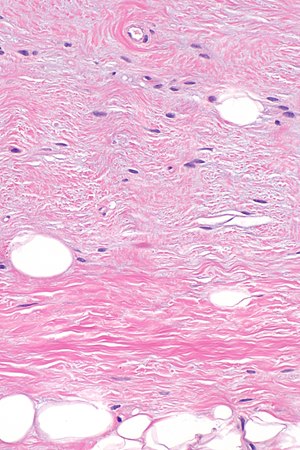

Micrograph showing a spindle cell lipoma. H&E stain. | |

| LM | aligned bland spindled cells adjacent to fat, rope-like collagen bundles (key feature), +/-myxoid component, +/-staghorn-like vessels |

- Aligned bland spindled cells adjacent to fat.

- Rope-like collagen bundles - key feature.

- May be described as "shreaded wheat".

- +/-Myxoid component.

- +/-Staghorn-like vessels.